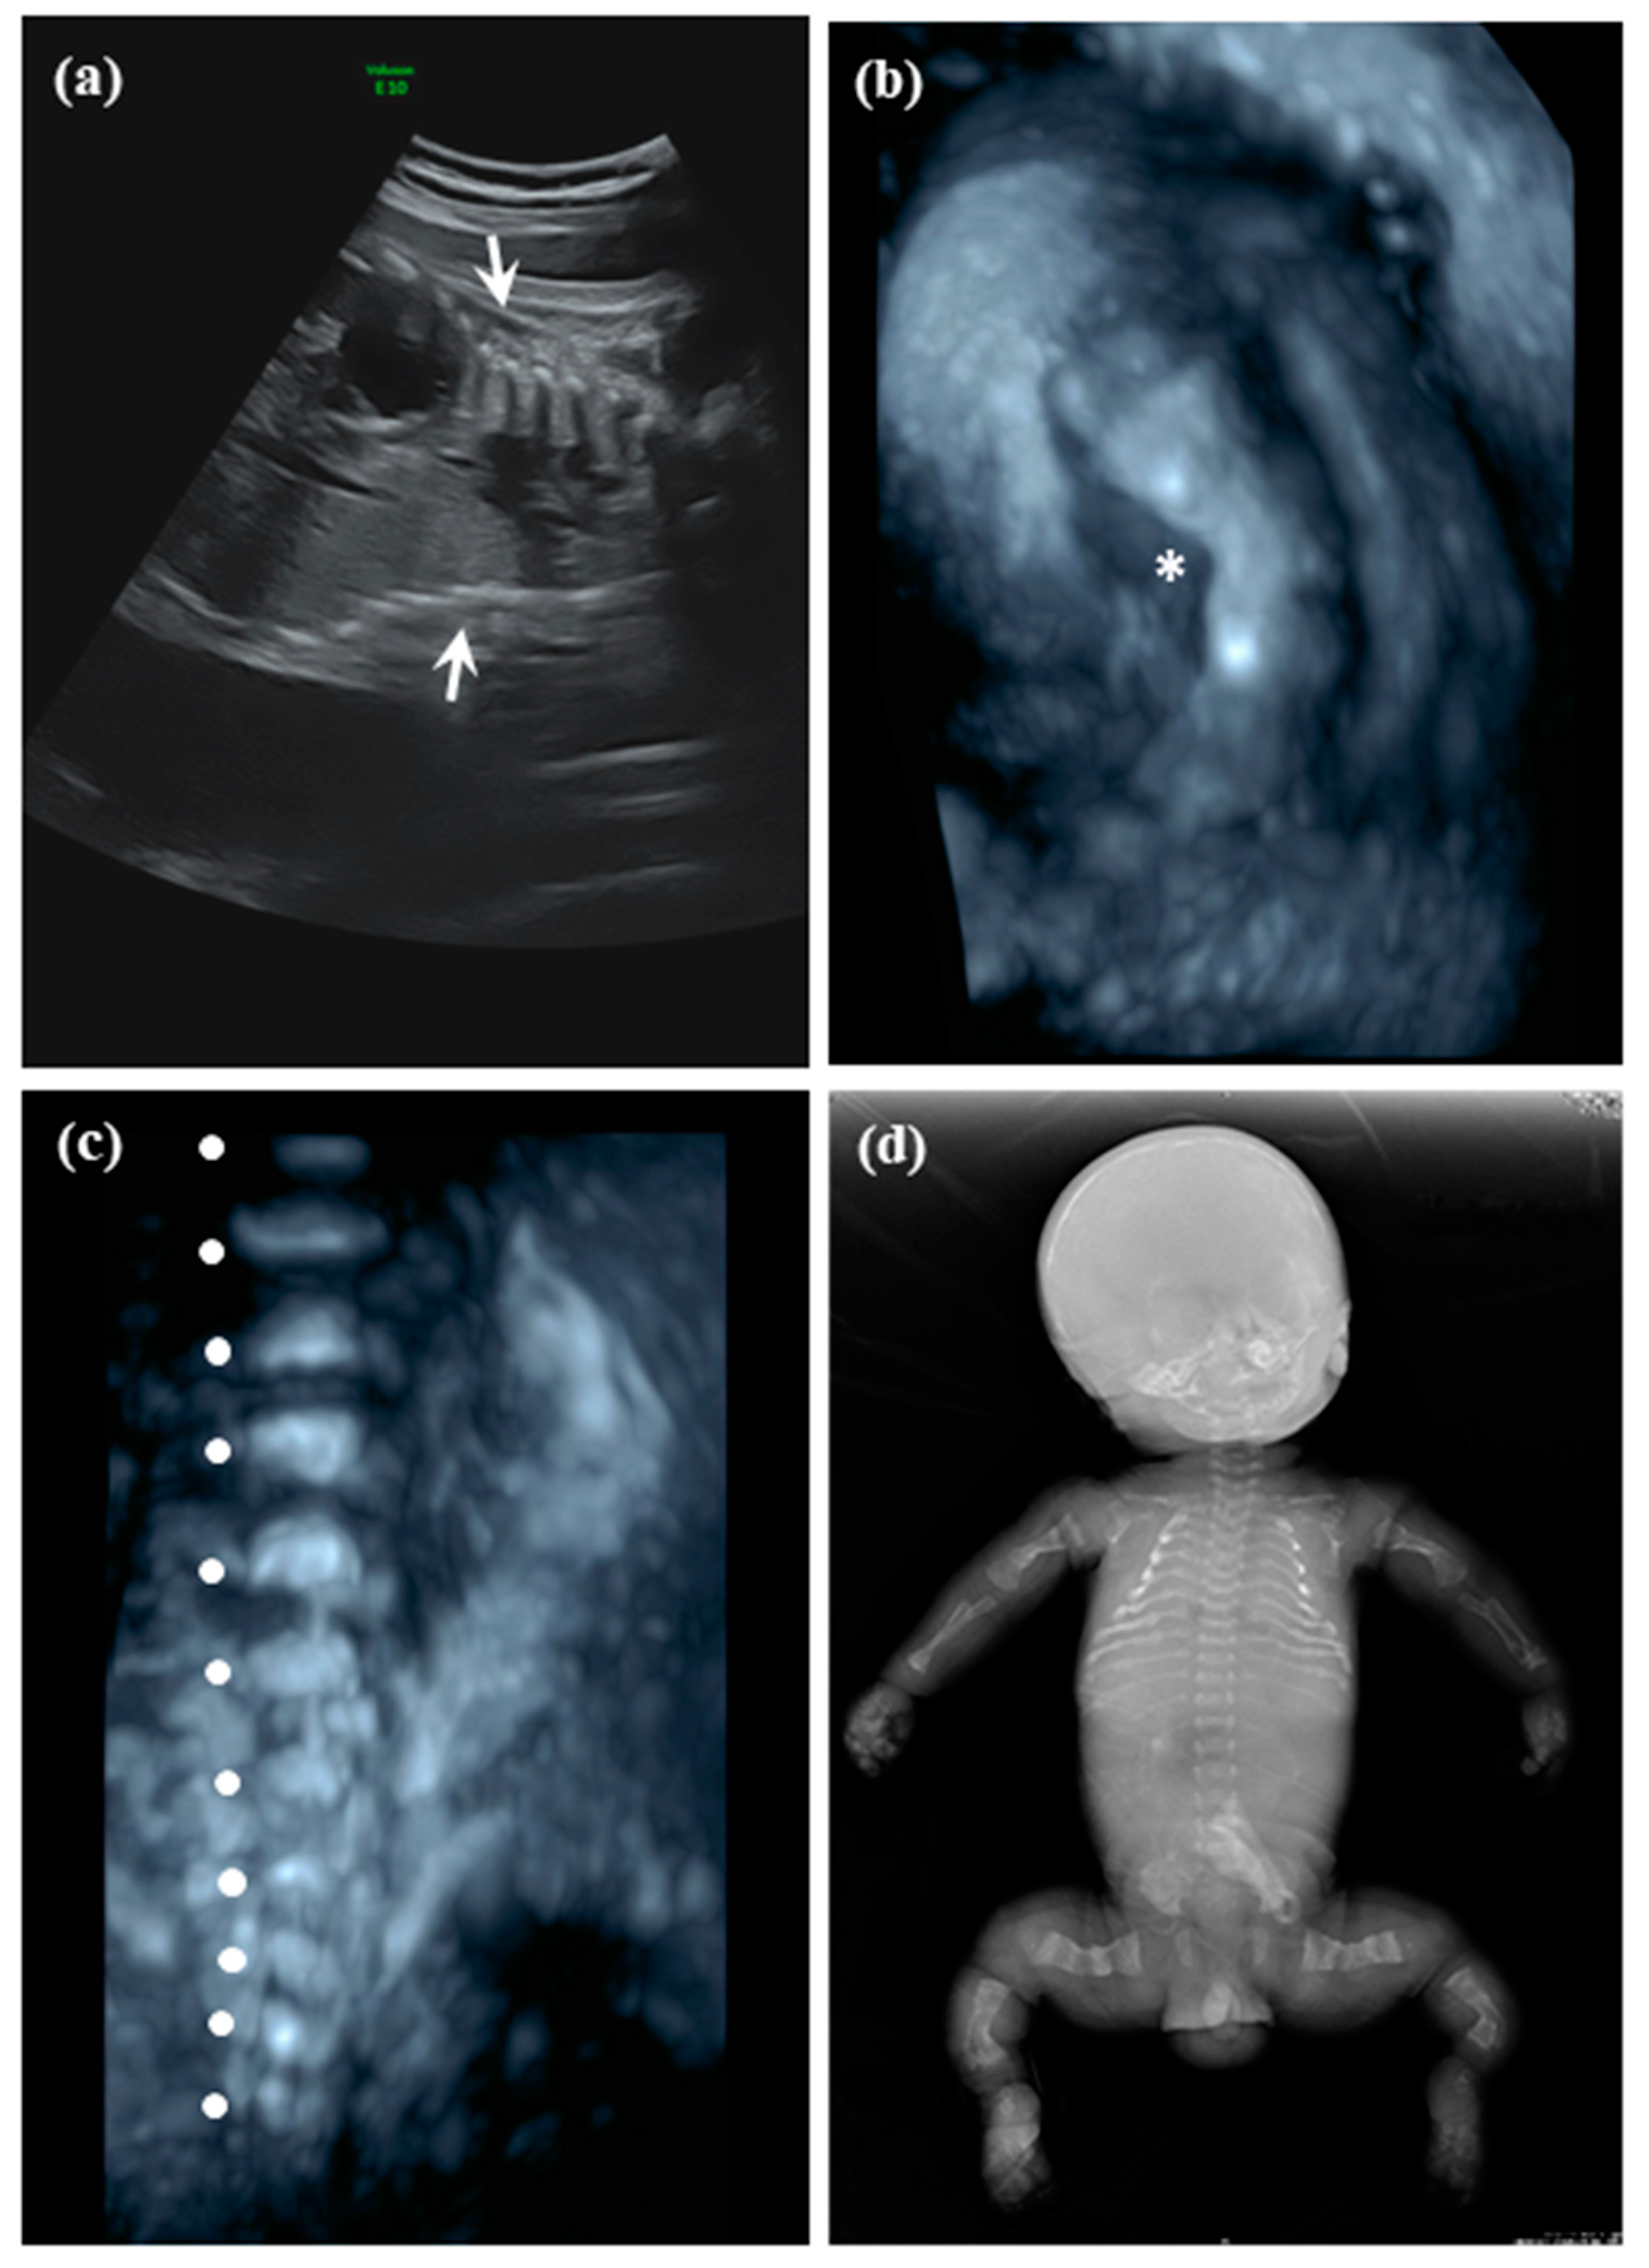

2.1.1. Patient 1

2.1.2. Patient 2